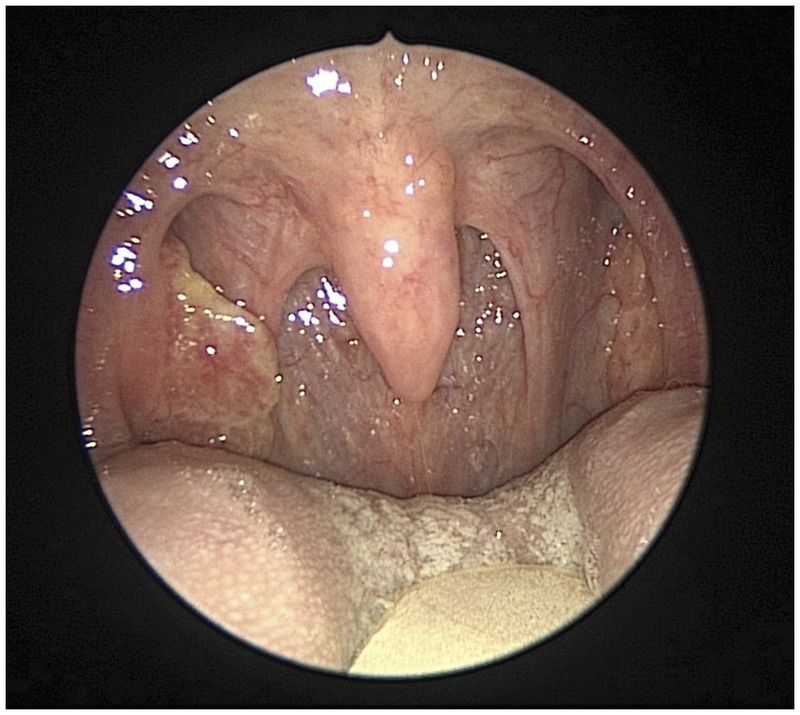

A 60-year-old man presented to the otolaryngology clinic with a firm mass on the right side of his neck that had been present for 2 months. He had no history of smoking or heavy alcohol use. The patient was otherwise asymptomatic, with no changes in his voice and no pain or difficulty with swallowing. Examination of the oropharynx revealed an asymmetrically enlarged right tonsil. A biopsy specimen of the tonsil was obtained and revealed invasive, nonkeratinizing, squamous-cell carcinoma. Strong nuclear and cytoplasmic expression for p16 was detected on immunohistochemical analysis, a finding consistent with human papillomavirus as the etiologic agent. Not every patient with primary tonsil cancer presents with a visible lesion; tumors may be hidden in the tonsil crypts. Induction chemotherapy and immunotherapy were initiated, followed by surgical resection of the cancer and neck dissection. Radiation therapy was avoided. On follow-up at 6 months, the patient was disease-free, had returned to work, and was eating a regular diet.